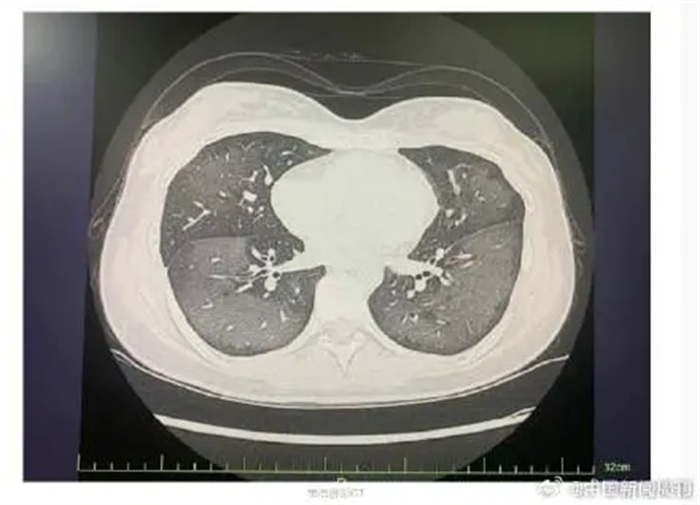

急诊科童娅玲主治医师接诊了丽丽,经CT检查发现,丽丽的双肺呈现大范围白色样病变,报告提示“白肺”。丽丽被诊断为“急性过敏性肺炎”,急诊专家对丽丽给予吸氧、激素抗炎抗过敏等对症支持处理后,急性症状得到缓解,她被收入呼吸内科病房进一步住院治疗。

急诊科主任陆远强主任医师解释,此类“白肺”与使用防晒喷雾时吸入的有害物质有关,喷雾中的某些化学成分会刺激诱发一系列过敏反应,从而导致广泛的气管、支气管乃至肺水肿,让肺部无法正常工作。